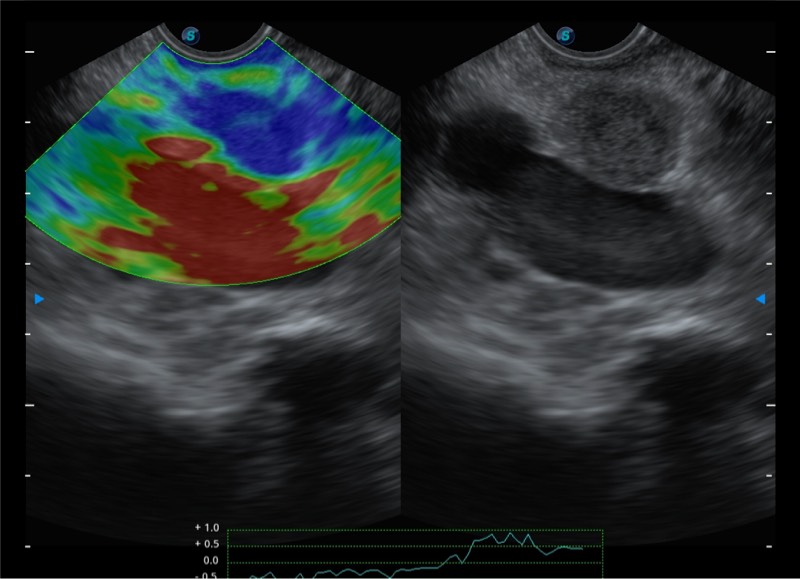

基于二十年的超声技术积累,1xBET提供了最新一代的独立超声主机,在提供高质量图像的同时满足多学科使用。具备常见多普勒技术并提供弹性成像、声学造影等高端影像技术。新一代传感器具有更强的抗干扰能力并减少图像伪影。